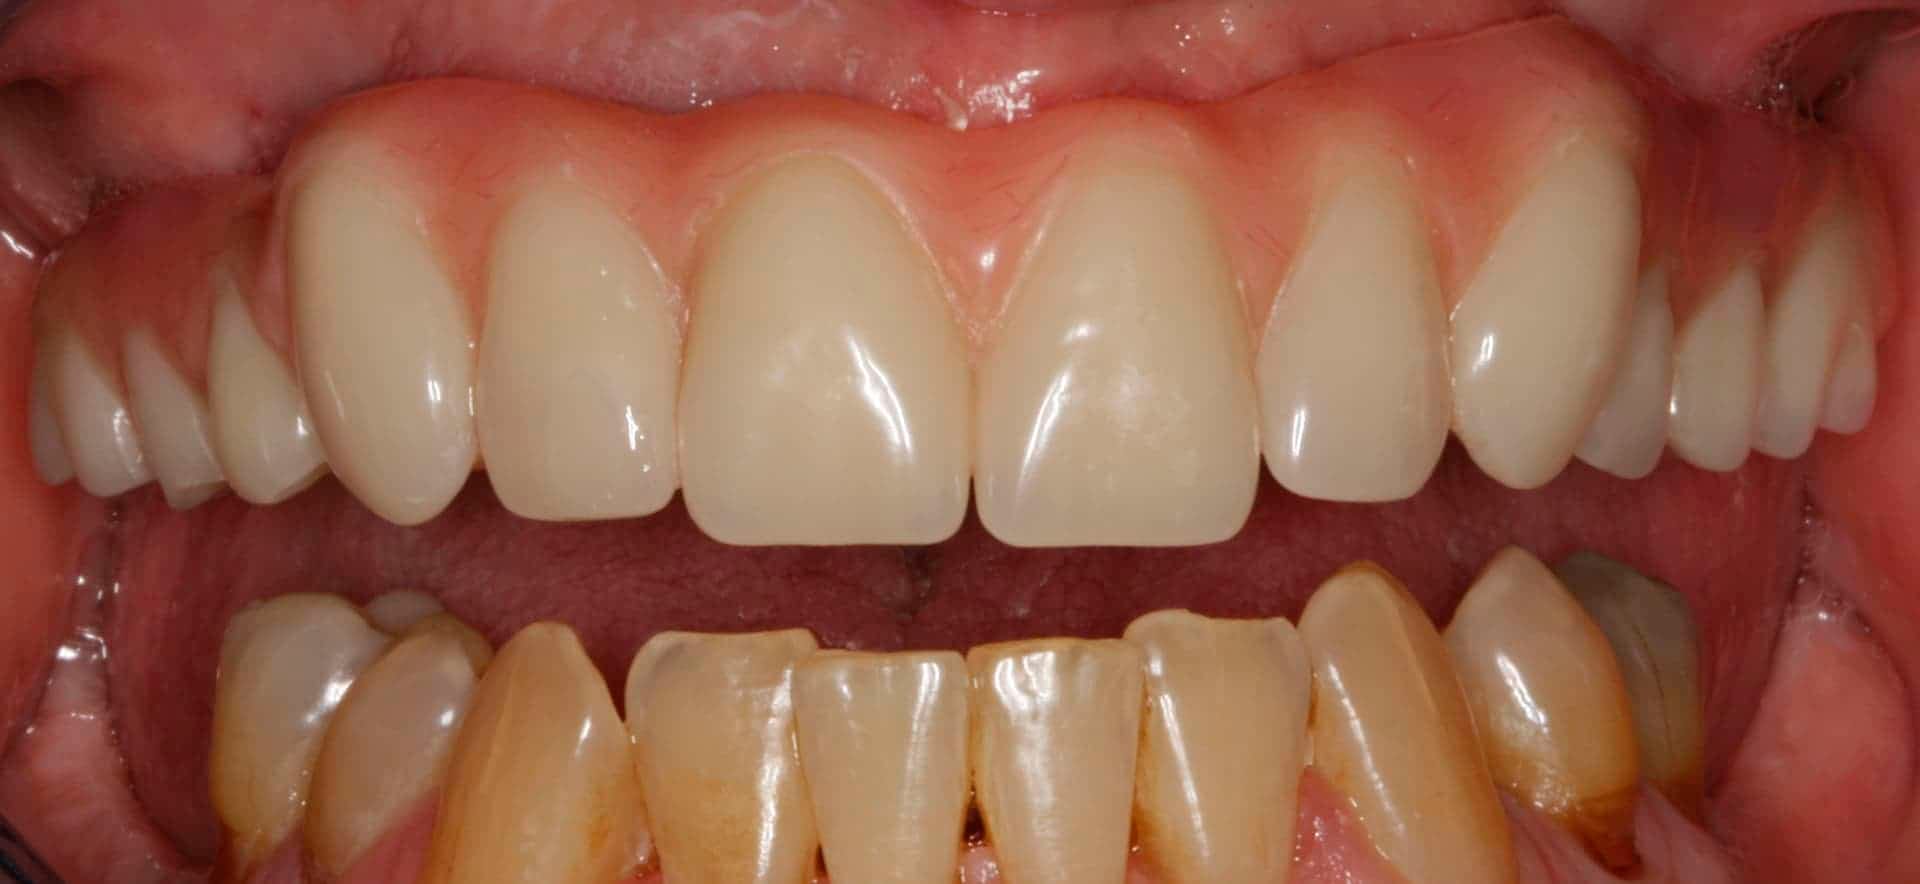

Before: Failed upper remaining teeth requiring removal. Patient elected to proceed with Phase I immediate complete denture therapy with the view toward phase II implant therapy.

After: Maxillary (upper), acrylic fused to metal, fixed (hybrid) screw-retained (retrievable) restoration supported by 6 titanium root form dental implants. The restoration is fixed, therefore only Dr. Leopardi can remove it for routine maintenance and hygiene, as needed. The patient cleans the fixed restoration as he does his natural lower teeth, with a tooth-brush, floss and water-pick. The outcome is improved function, mastication/diet, aesthetics and quality of life.